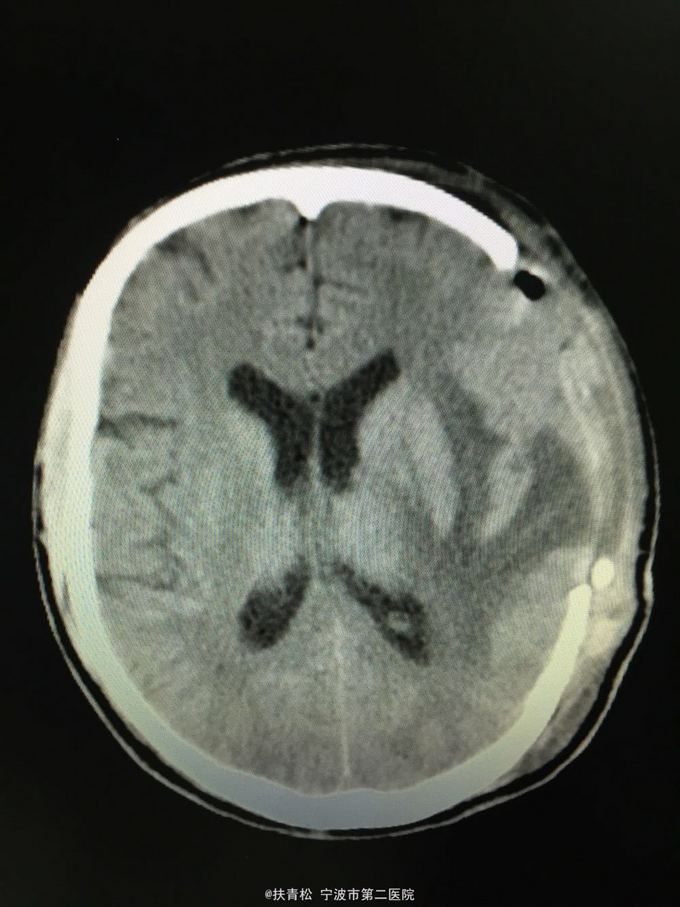

脑胶质瘤

左颞叶胶质瘤

头痛三月余,复发加重一月

行左颞叶胶质瘤切除术